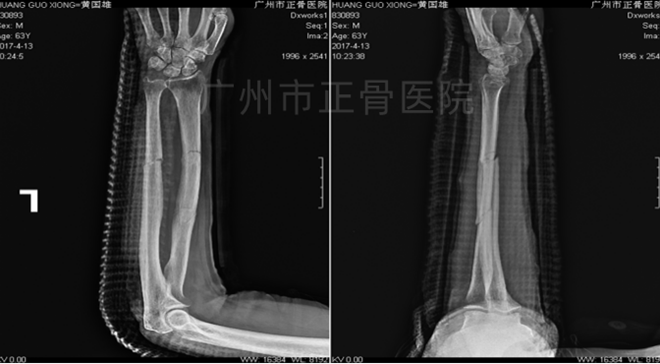

▲1周后,骨折端稳定

▲4周后,骨折端稳定,少量骨痂生长

▲6周后,骨痂增多